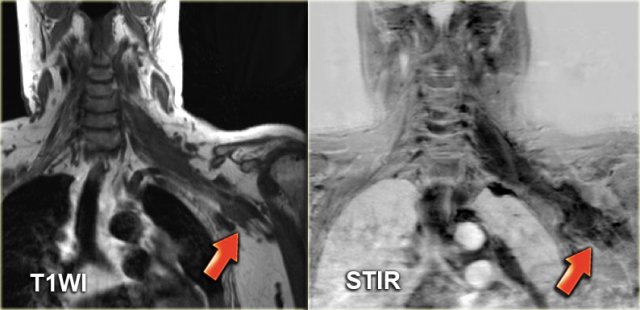

On the left a longitudinal and transverse image fo a large second branchial cleft cyst in a 12-year old girl situated between the parotid gland (left image) and the submandibular gland (right image).

It is superficial to the carotid artery and jugular vein (arrow).

The cyst contents is hypoechoic with freely moving debris.

The MR of the same patient confirms the presence of a cystic mass in the right carotid space.

The lesion is situated between the submandibular gland and the anterior margin of the sternocleidomastoid muscle, which is the classic position of a second branchial cleft cyst.

The lesion shows edge enhancement post-Gadolinium.

Notice that these lesions may contain small amounts of lymphoid tissue which is a possible explanation for the small area of enhancement inside the cyst wall (arrow).

Coronal STIR image of the same cyst.